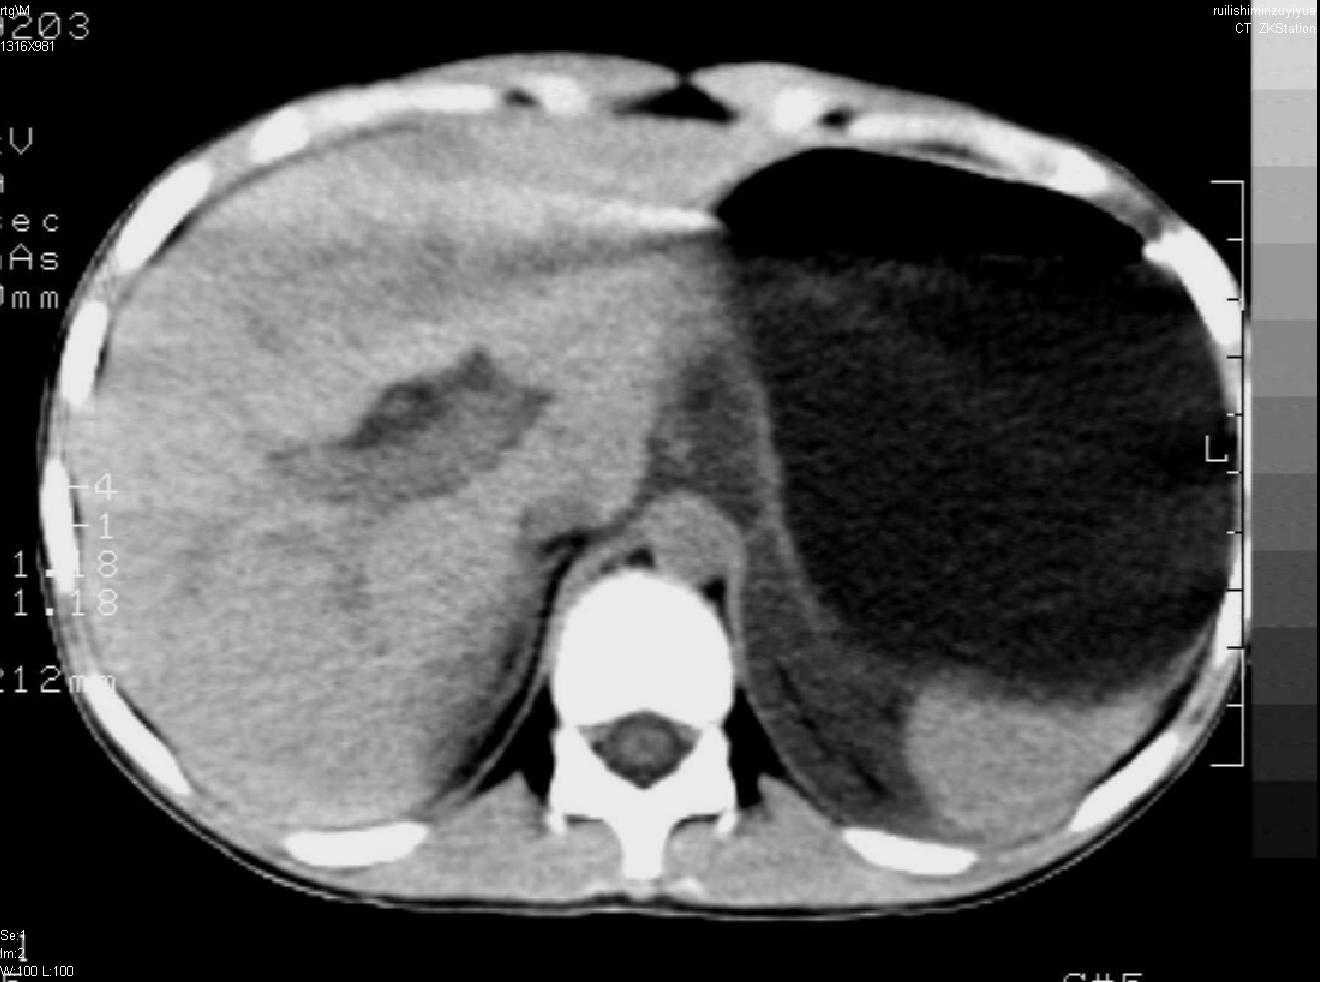

标题: PED0282:女,10岁,上腹疼痛2周 [打印本页]

标题: PED0282:女,10岁,上腹疼痛2周

b超:胆囊结石。疑坏死性胰腺炎

支持小儿急性坏死性胰腺炎。

支持急性胰腺炎。

支持急性胰腺炎并腹膜炎。

急性胰腺炎,腹腔积液